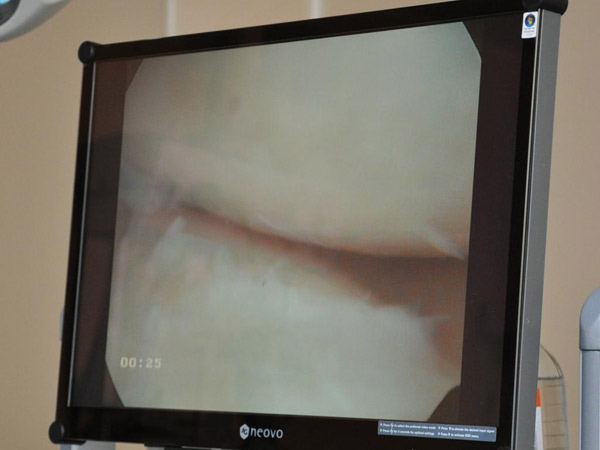

"сама операция"